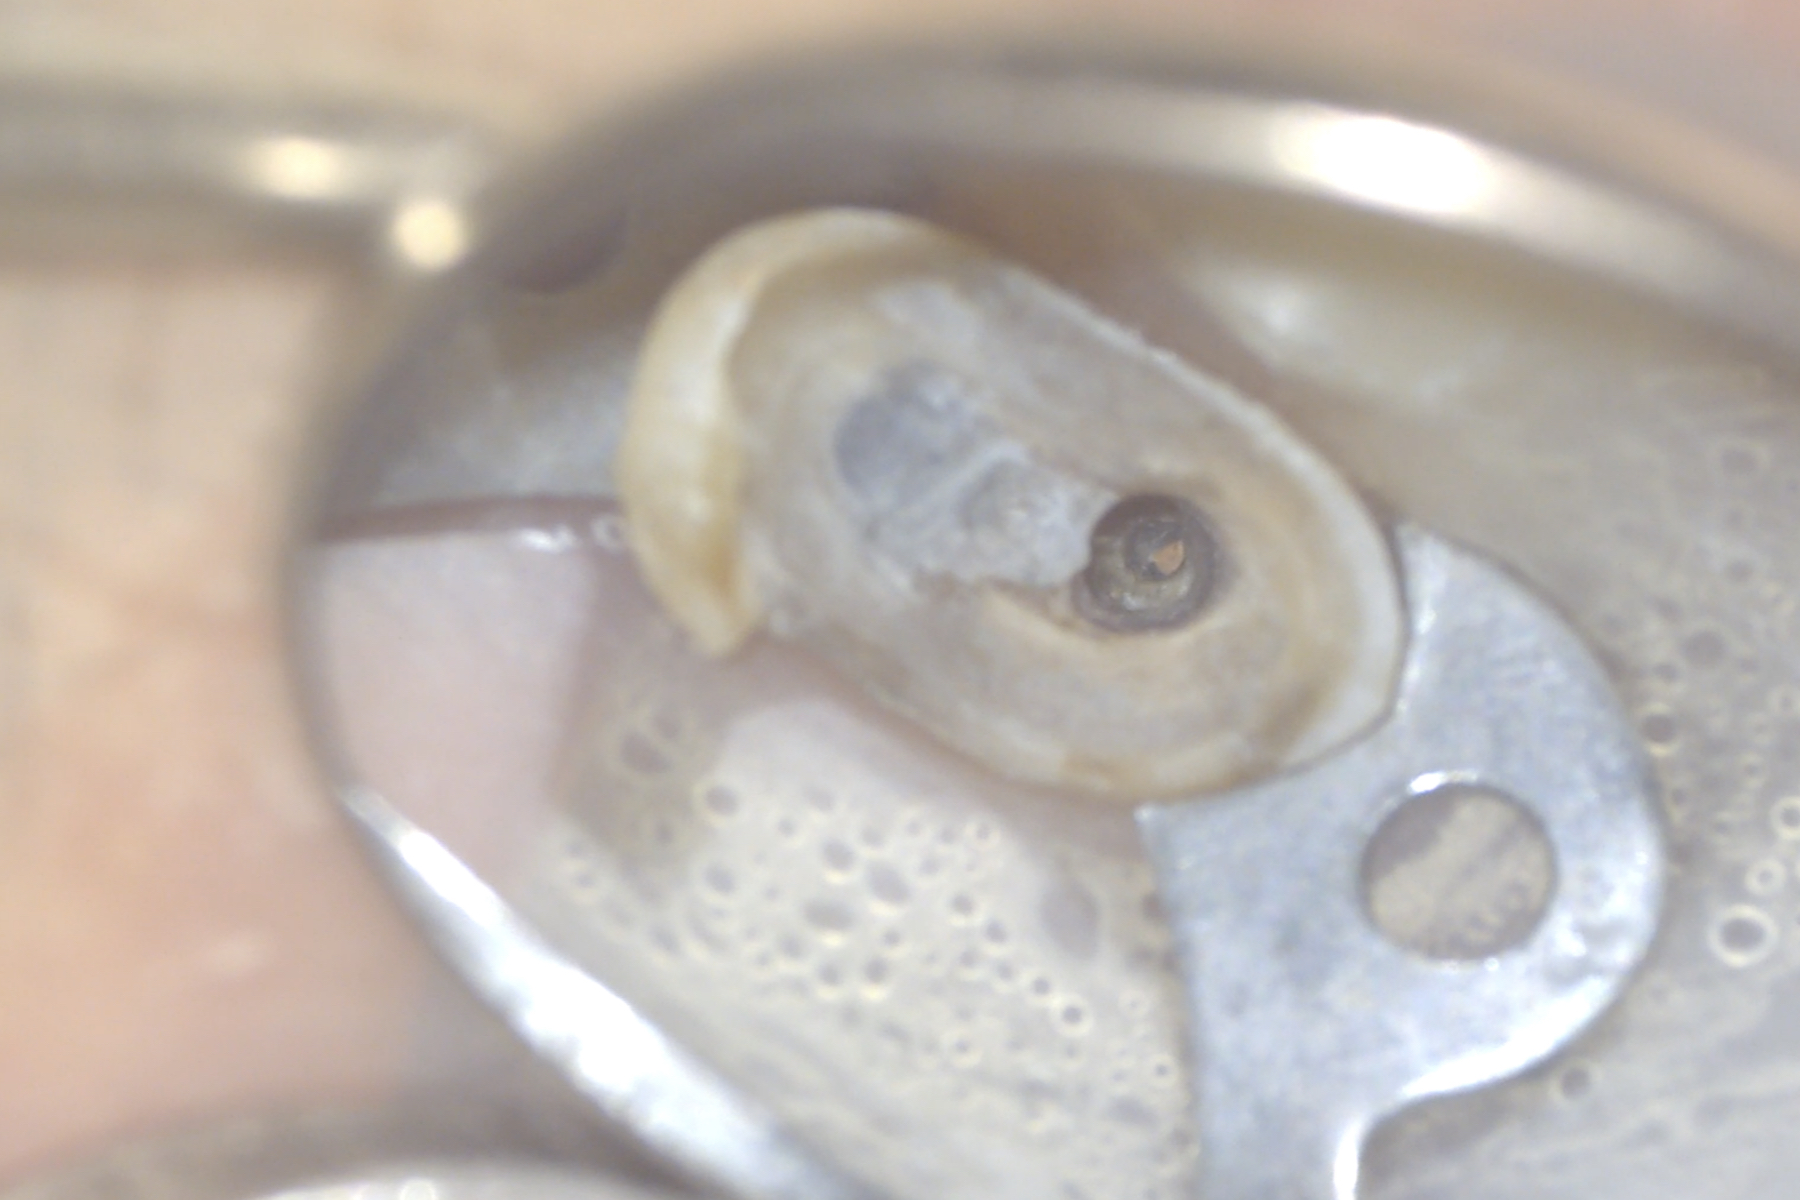

Visualizzata la guttaperca intracanalare con core plastico (Figura 4) viene completato lo svuotamento dei canali (Figura 5) mediante strumenti rotanti Protaper Gold (Dentsply-Sirona); effettuata la misurazione elettronica della lunghezza di lavoro, si procede con la strumentazione degli interi canali con tecnica step-down.